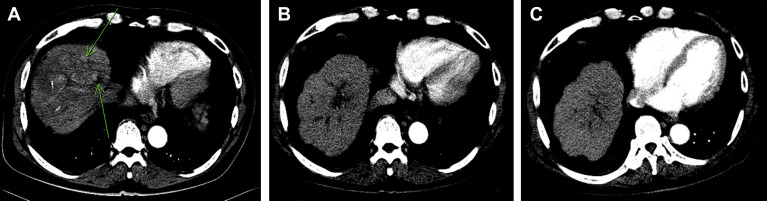

A 65-year-old man was a victim of alcoholic liver cirrhosis (Child–Pugh class B) with ascites under diuretics (oral furosemide 80 mg and spironolactone 200 mg daily) control and received periodic HCC surveillance every 4 months for 14 years. Unfortunately, his α-fetoprotein (AFP) level was highly elevated and abdominal ultrasonography detected multiple liver tumors in November 2005. Physical examination revealed jaundice, mild hepatomegaly with a span of 13 cm on the right middle clavicle line and an irregular margin with a hard consistency that measured 2 cm below the right costal margin. The spleen was impalpable. No fever, skin rash, ascites, spider angioma, or palmar erythema was noted. Laboratory studies disclosed the following results: hemoglobin, 13.5 g/dL; leukocytes, 5.2 × 109 /L; platelets, 110 × 109 /L; albumin, 3.6 g/dL, globulin, 3.1 g/dL; total bilirubin, 4.2 mg/dL (normal, <1.3 mg/dL); serum aspartate aminotransferase (AST), 222 U/L (normal, <34 U/L); serum alanine aminotransferase (ALT), 51 U/L (normal, <36 U/L); alkaline phosphatase, 210 IU/L (normal, <94 IU/L); prothrombin time, 12.4 seconds (control, 10.0 seconds); international normalized ratio, 1.12; and AFP 4935 ng/mL (normal < 3 ng/mL). Hepatitis B surface antigen and antibody to hepatitis C virus were both negative. Abdominal ultrasonography showed multiple hyperechoic and mixed echoic tumors in cirrhotic parenchyma, the largest being 5.9 cm in diameter, without the presence of ascites. Dynamic computed tomography (CT) showed multiple arterially enhanced tumors, mainly in the right lobe having a portal- and delayed-phase washed-out appearance. The invasion of tumors into the main portal trunk and its proximal branches with suspicion of biliary tree compression are shown in Fig. 1 A. The tumors were considered HCCs because of the presence of the characterized arterial vascularization and rising AFP levels. This patient appeared to be asymptomatic and was staged as Barcelona Clinic Liver Cancer (BCLC) stage C.

(A) Prior to thalidomide therapy, multiple arterially enhanced tumors were located in the right lobe (arrow), and multiple infiltrating tumors were located in the central portion of the liver with portal vein thrombi. (B) Follow-up examination after 4.5 months of thalidomide therapy showed complete remission of liver tumors and significant regression of portal vein thrombi. (C) Follow-up examination after 20 months of thalidomide therapy showed complete remission of liver tumors and portal vein thrombi.

The patient was assessed as inoperable and unsuited for TACE or systemic chemotherapy. Attending a clinical trial with target therapy was suggested initially, but the patient refused. He agreed to receive thalidomide (50 mg capsule; TTY Biopharm, Taipei, Taiwan) 50 mg twice daily after obtaining written informed consent and followed at an outpatient clinic. Three weeks after thalidomide therapy, he occasionally complained of skin eruptions with itching. There was no fever, nausea, constipation, vomiting, fatigue, or somnolence. Laboratory studies disclosed the following: AST, 436 U/L; ALT, 94 U/L; total bilirubin, 5.2 mg/dL; and serum AFP, 7350 ng/mL. He continued to take thalidomide 100 mg daily without specific complaint. Follow-up liver biochemical tests after 3 months of thalidomide therapy showed the following: AST, 44 IU/L; ALT, 29 IU/L; total bilirubin, 1.8 mg/dL; and serum AFP, 13 ng/mL. The clinical course is shown in Fig. 2 . Dynamic CT showed significant regression of the portal vein thrombi and complete remission of tumors 4.5 months after initial diagnosis (Fig. 1 B). Thalidomide dose was reduced to 50 mg daily after 9 months treatment because of serum AFP and ultrasonography showing no evidence of HCC recurrence. Abdominal CT or ultrasonography at 20 months after thalidomide therapy showed complete tumor regression (Fig. 1 C). The AST, ALT, and AFP levels remained within normal limits. Unfortunately, he succumbed to a perforated duodenal ulcer with multiple organ failure 22 months after initial diagnosis.